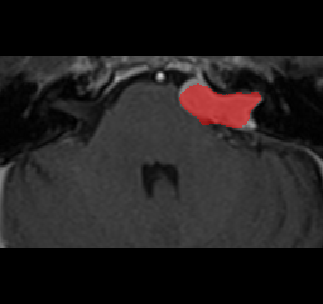

Recently, deep learning methods have achieved state-of-the-art performance in many medical image segmentation tasks. Many of these are based on convolutional neural networks (CNNs). For such methods, the encoder is the key part for global and local information extraction from input images; the extracted features are then passed to the decoder for predicting the segmentations. In contrast, several recent works show a superior performance with the use of transformers, which can better model long-range spatial dependencies and capture low-level details. However, transformer as sole encoder underperforms for some tasks where it cannot efficiently replace the convolution based encoder. In this paper, we propose a model with double encoders for 3D biomedical image segmentation. Our model is a U-shaped CNN augmented with an independent transformer encoder. We fuse the information from the convolutional encoder and the transformer, and pass it to the decoder to obtain the results. We evaluate our methods on three public datasets from three different challenges: BTCV, MoDA and Decathlon. Compared to the state-of-the-art models with and without transformers on each task, our proposed method obtains higher Dice scores across the board.